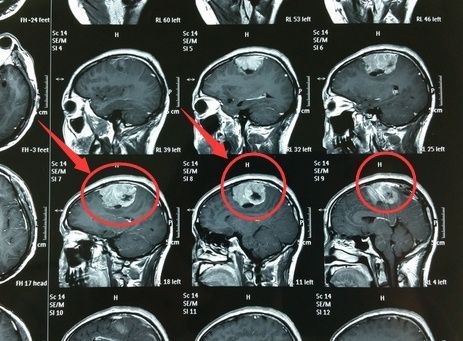

常见囊性变和出血坏死,有包膜,属脑外肿瘤

脑转移瘤

小脑转移瘤